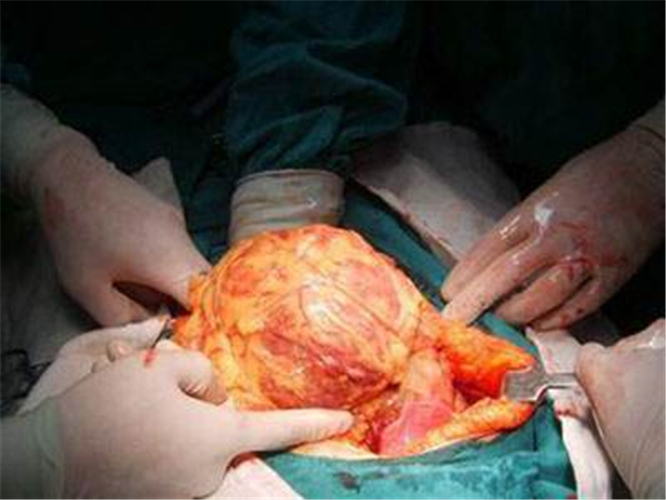

雙腎巨大腎囊腫

手術切除腎囊腫

腎囊腫引起腎巨大